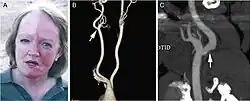

A man exhibiting the asymmetric symptoms of Harlequin syndrome. One half of the forehead is more red than the other.

Harlequin syndrome, also known as "harlequin sign", is a condition characterized by asymmetric sweating and flushing on the upper thoracic region of the chest, neck and face. Harlequin syndrome is considered an injury to the autonomic nervous system (ANS). The ANS controls some of the body's natural processes such as sweating, skin flushing and pupil response to stimuli.[1] Individuals with this syndrome have an absence of sweat skin flushing unilaterally, usually on one side of the face, arms and chest. It is an autonomic disorder that may occur at any age.[2]

The "Harlequin sign" is unilateral flushing and sweating of the face, neck, and upper chest usually after exposure to heat or strenuous exertion.[6] Horner syndrome, another problem associated with the sympathetic nervous system, is often seen in conjunction with harlequin syndrome.